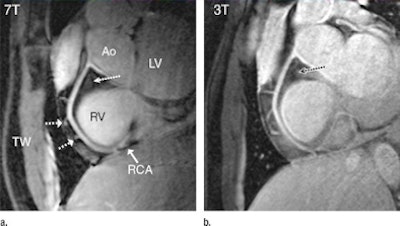

| 7-tesla (a) and 3-tesla MR (b) angiograms of the RCA in a healthy 18-year-old male show improved suppression of epicardial fat (long dotted arrow), with high contrast between the blood and epicardial fat visible at 7 tesla. At both field strengths, a number of small branching vessels are depicted (short dashed arrows). Also at 7 tesla, a long portion of the RCA is visible (solid arrow = distal part of RCA). Ao = aortic root, LV = left ventricle, RV = right ventricle, and TW = thoracic wall. All images courtesy of Radiology. |

In evaluating the MRI scans, van Elderen and colleagues found that all images displayed a high signal intensity of the coronary artery lumen, while that of the surrounding epicardial fat was suppressed. Using 7-tesla MRI, suppression of the epicardial fat was visually improved when compared with 3 tesla. In addition, the quantitative C/N ratio between the blood pool and epicardial fat was significantly improved at 7 tesla.

When compared with 3-tesla MRI, the S/N ratio of the blood pool measured on the 7-tesla images was 60% higher, with improved delineation of the right coronary artery at 7 tesla and good depiction of RCA branches and distal segments. Objective vessel sharpness analysis also demonstrated improved quantitative vessel conspicuity at 7 tesla, the authors wrote.